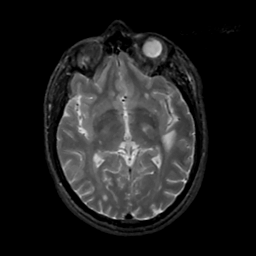

MR Study #2, February 17, 1991 -- Slice #24

[Home][Help][Clinical][Tour 1][Tour 2] Slice 24